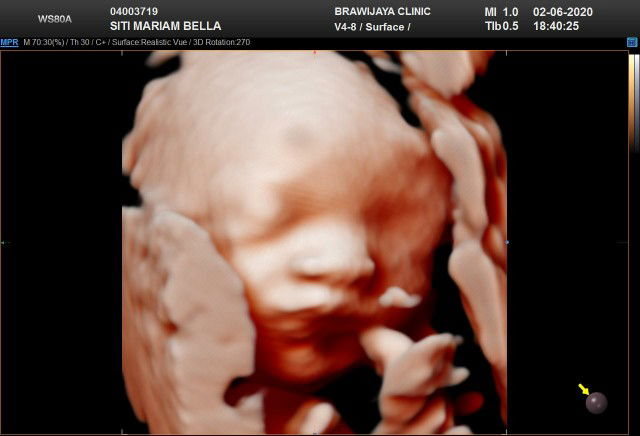

Assalamu'alaikum bunda.. disini apakah ada yg sama juga sprti saya hplnya bulan juli?? Trakhir saya usg tgl 2juni dan bbjnya baru 2,1kg bun ? jujur saya sempet agak down krna takut nanti bayi saya lahir bbnya kurang dari seharusnya. Usia kehamilan saya skrg 34minggu